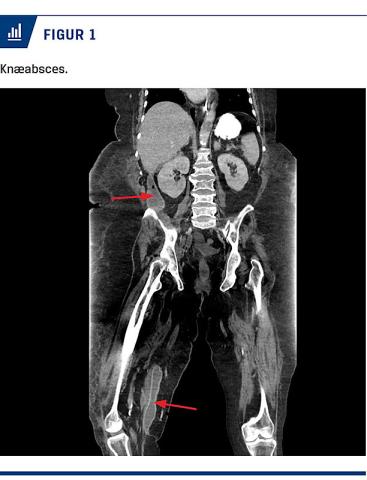

Højre UE hævede yderligere, og 27 dage efter indlæggelse blev der foretaget endnu en CT, som viste tiltagende væskeansamling ved pancreas og i højre fossa, samt multiple abscesser i lårmuskulaturen på højre UE (Figur 1). Ansamlingen i UE blev dræneret lige over knæniveau (Figur 2) med udtømning af 400 ml pus (der indeholdt 34 IE amylase), og ansamlingen i højre fossa blev tømt ultralydvejledt. Begge ansamlinger indeholdt Escherichia coli, hæmolytiske B-streptokokker og Staphylococcus aureus, hvilket medførte et længerevarende behandlingsforløb med firestofsantibiotika. Med tilstedeværelsen af amylase blev abscesserne tolket som sænkningsabscesser gennem retroperitonealrummet ned mod højre UE – altså en ekssudativ pankreatitis.